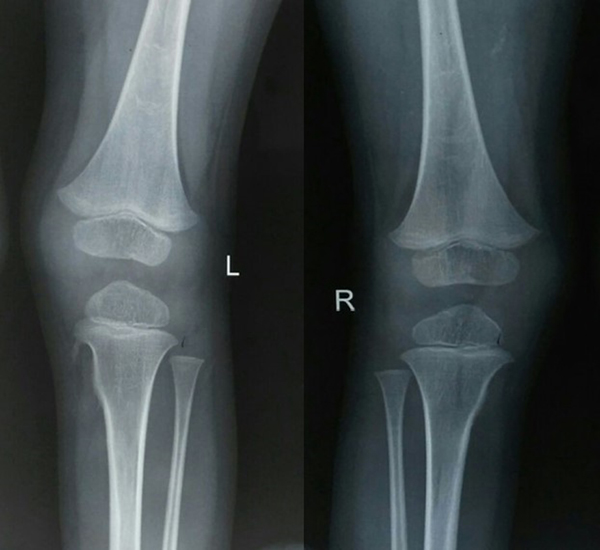

Physical examination revealed bilateral shortening and valgus deformity of the great toes (Figure 1). Multiple swellings of variable size were present on occiput, nape of neck, bilateral scapular area, bilateral axilla and midback. Swellings were non tender, hard, smooth, mobile with well-defined edges and were lying in subcutaneous tissues & muscles. Movements of the neck and bilateral shoulder were decreased (Figure 3). Rest of the joints including bilateral hips, elbows, wrists, knee, and ankle were normal. A radiograph of the right shoulder showed osteomas between the scapula and the proximal end of the humerus (Figure 4). Cervical spine radiographs revealed large posterior elements, narrow vertebral bodies and loss of cervical lordosis (Figure 5). Radiograph of the dorso-lumbar spine revealed large ectopic bone mass bridging the lower dorsal and lumbar spine (Figure 6). Radiograph of the knees revealed the presence of osteochondromas of the proximal medial end of the tibia (Figure 7). Lab findings were normal except for raised ESR (50mm in first hour) & liver enzymes were mildly raised. Patient was diagnosed as a case of FOP on the basis of clinico-radiological examinations. Biopsy was not done because of the fear of flaring up of the disease. Oral prednisolone was given in a dose of 2mg/kg for 5 days. Acute flare of the disease settled and the patient was discharged with advice of regular follow-ups.

Figure 7 Radiograph of the knees revealed the presence of osteochondromas of the proximal end of the tibia (medial aspect).

Plain radiographs show ectopic ossifications of soft tissues. Cervical spine radiographs reveals large posterior elements, tall narrow vertebral bodies, and fusion of the facet joints with frank bony ankyloses.1,17 Advanced disease shows bony bridges across the spine and joints rendering movements impossible as was seen in our patient. Other abnormalities features are short malformed thumbs, clinodactyly, short broad femoral necks, and proximal medial tibial osteochondromas.18 ACT scan can be useful to better analyze ossifications; MRI and technetium bone scan can show lesions at an initial stage, when they are not yet ossified. Laboratory investigations generally do not reveal any significant abnormality.